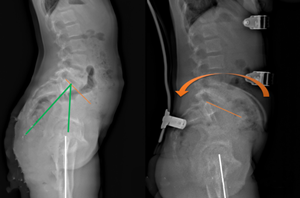

5、矢狀面靜態(tài)平衡,對矢狀面生理曲度的控制,減少平背,腰椎過度前凸的產(chǎn)生。,在全脊柱側(cè)位片上分別測量骨盆入射角(IP)、骨盆傾斜角(VP)、骶骨傾斜角(PS)、腰椎前凸角(LL)、胸椎后凸角(TK)的度數(shù),以骨盆入射角為參考下方的尺子對應(yīng)其他幾個(gè)角度的值是否在該線上,來判斷患者的矢狀面生理曲度是否處于平衡狀態(tài)。